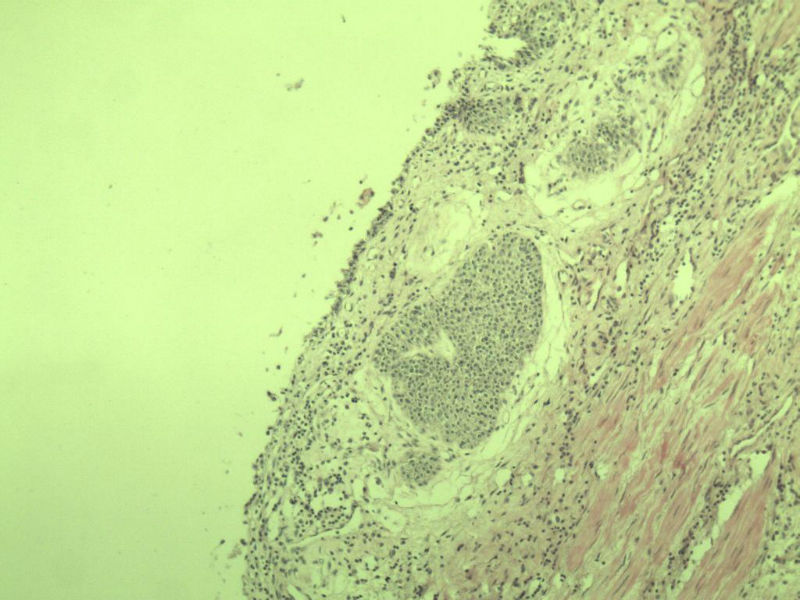

男 75岁 因排尿困难半年行前列腺切除术,体积 4 × 3 × 2.5 cm3,切面灰白,实性,质韧。请各位老师看看 有问题没? 谢谢了!

高级别上皮内瘤变,建议免疫组化:P63、34BE12、P504S

前列腺增生症伴鳞化

良性前列腺增生伴尿路上皮化生

前列腺增生伴尿路上皮鳞化及Brown巢形成,未见恶性。